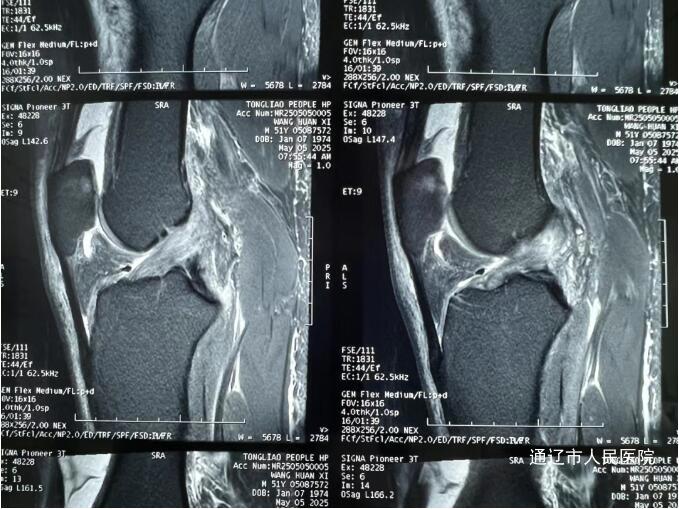

术前

(前交叉韧带损伤MRI图像)